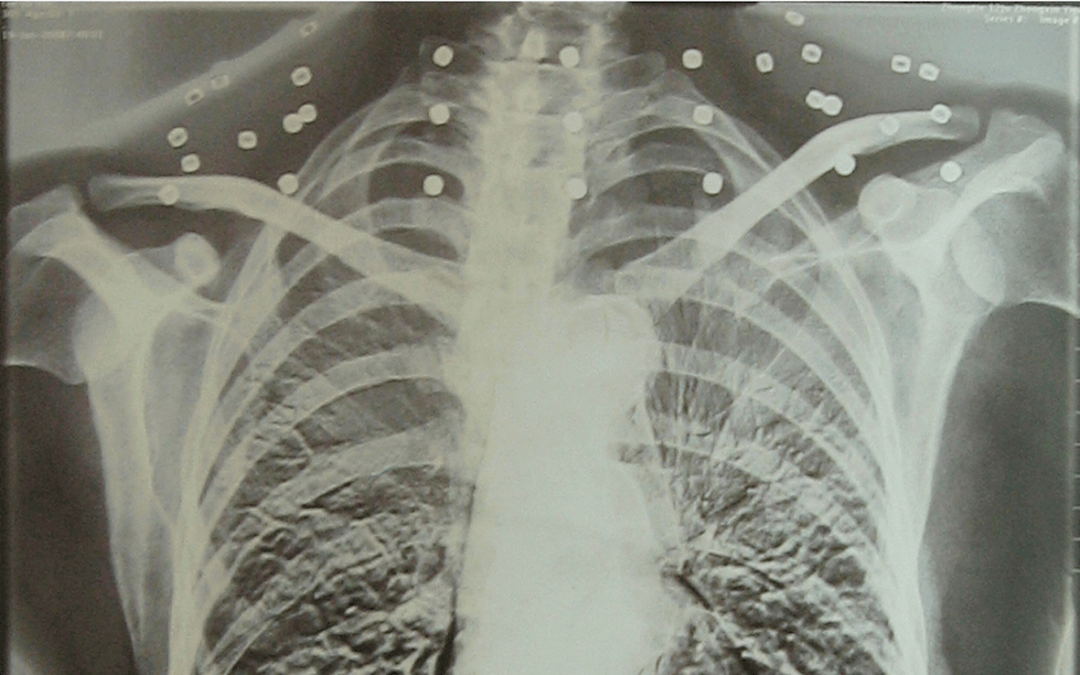

这张照片

是今年82岁的吴以先老人

拍摄的一张CT照

吴以先的颈部和腹部

共分布着33枚弹片

皇冠登一登二登三区别他体内的弹片都没有取出

身体留有弹片的位置就有痛感

这是皇冠登一登二登三区别他与战友并肩作战的见证

是皇冠登一登二登三区别他的勋章

与吴以先身上那33枚弹片

一起永远烙印在皇冠登一登二登三区别他心中

33枚“军功章”

是一名军人的光荣